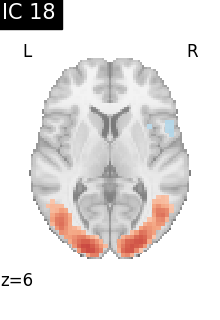

Finally, we plot the map for each ICA component separately

from nilearn.image import iter_img

from nilearn.plotting import plot_stat_map, show

for i, cur_img in enumerate(iter_img(canica_components_img)):

plot_stat_map(

cur_img,

display_mode="z",

title=f"IC {int(i)}",

cut_coords=1,

vmax=0.05,

vmin=-0.05,

colorbar=False,

)

show()